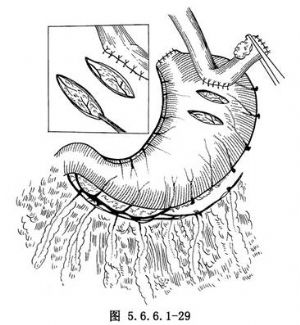

(2)在胃底距边缘约3cm处大弯与小弯之间作一宽度与食管相等的横切口直至黏膜下层但勿切开黏膜,再在其远侧3cm处另作一等大的平行切口,用剪刀将此两个切口之间位于黏膜下层与浆肌层中间的结缔组织间隙打通,用细丝线将第2个切口内的黏膜下血管缝扎两处。将肿瘤上方6cm处的正常食管后壁用丝线间断固定在第一个横切口的上方胃壁上(图5.6.6.1-29)。以后将胃黏膜由第2个切口下两个血管缝扎线之间切开。